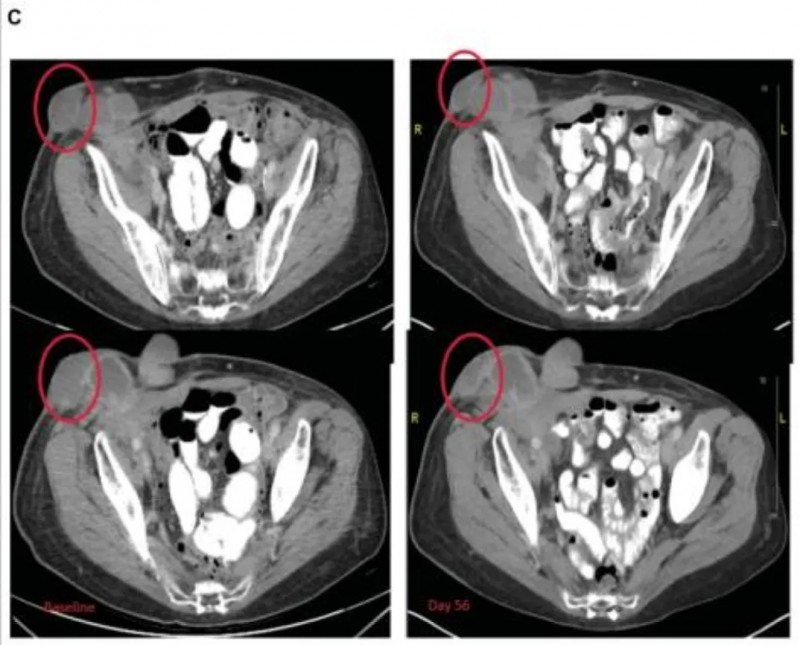

值得特别关注的是1例63岁浆液性输卵管/卵巢癌患者:该患者此前已接受过13线全身治疗,虽按RECIST标准其最佳疗效判定为SD,但注射病灶在4次治疗后接近消退,周围未注射的病灶在治疗第4周期也明显变平(详见下图),展现出该疗法在局部病灶控制上的潜力。

▲图源“Oncologist”,版权归原作者所有,如无意中侵犯了知识产权,请联系我们删除